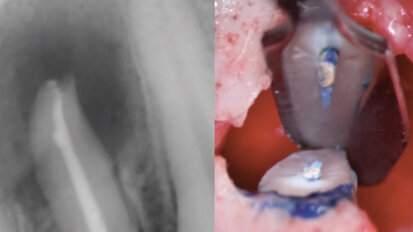

Nový úsměv za jeden den

Čt. 28. května 2020